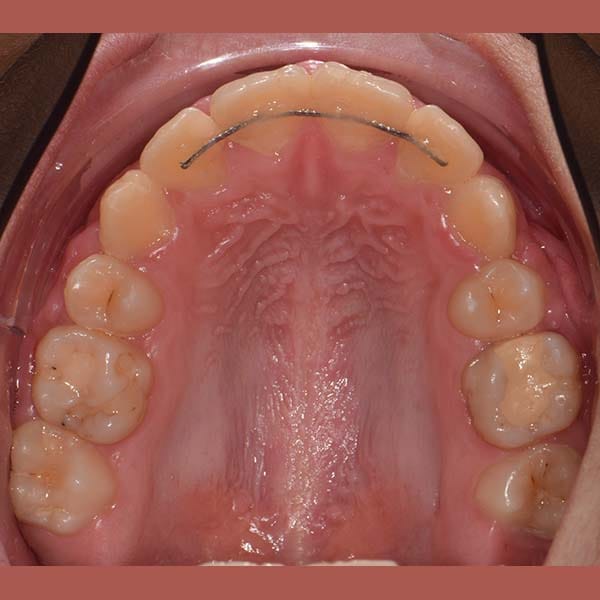

AFTER

This young woman suffered from an upper jaw stenosis, crowded teeth, and the absence of one of the upper molars.

She was treated with Daimon braces (an orthodontic device that doesn’t require rubber to fix the archwires, which reduces friction and speeds up treatment).

At the end of the treatment, we were able to see a clear expansion in her upper jaw, her teeth were aligned beautifully, and the gap resulting from the absence of the molar was closed orthodontically.